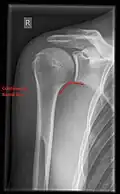

Imaging of the shoulder includes ultrasound, X-ray and MRI, and is guided by the suspected diagnosis and presenting symptoms.

Conventional x-rays and ultrasonography are the primary tools used to confirm a diagnosis of injuries sustained to the rotator cuff. For extended clinical questions, imaging through Magnetic Resonance with or without intraarticular contrast agent is indicated.

Hodler et al. recommend starting scanning with conventional x-rays taken from at least two planes, since this method gives a wide first impression and even has the chance of exposing any frequent shoulder pathologies, i.e., decompensated rotator cuff tears, tendinitis calcarea, dislocations, fractures, usures, and/or osteophytes. Furthermore, x-rays are required for the planning of an optimal CT or MR image.[25]

X-ray

Projectional radiography views of the shoulder include:

- AP-projection 40° posterior oblique after Grashey

The body has to be rotated about 30 to 45 degrees towards the shoulder to be imaged, and the standing or sitting patient lets the arm hang. This method reveals the joint gap and the vertical alignment towards the socket.[26]

- Transaxillary projection

The arm should be abducted 80 to 100 degrees. This method reveals:[26]

- The horizontal alignment of the humerus head in respect to the socket and the lateral clavicle in respect to the acromion

- Lesions of the anterior and posterior socket border, or of the tuberculum minus

- The eventual non-closure of the acromial apophysis

- The coraco-humeral interval

- Y-projection

The lateral contour of the shoulder should be positioned in front of the film in a way that the longitudinal axis of the scapula continues parallel to the path of the rays. This method reveals:[26]

- The horizontal centralization of the humerus head and socket

- The osseous margins of the coraco-acromial arch and hence the supraspinatus outlet canal

- The shape of the acromion

This projection has a low tolerance for errors and, accordingly, needs proper execution.[26] The Y-projection can be traced back to Wijnblath’s 1933 published cavitas-en-face projection.[27]